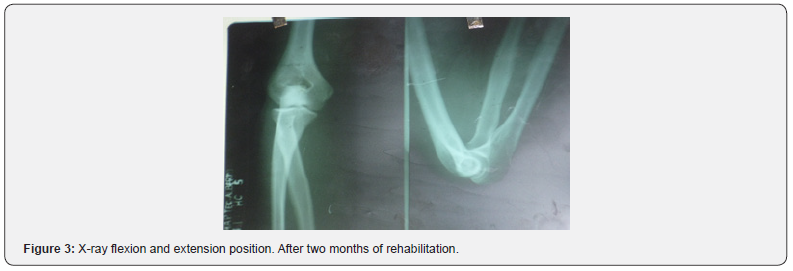

The patient was transferred to the operating room where reduction was carried out under anesthesia in the supine position. Two specialists intervened in the procedure, one of whom fixed the patient’s arm against the examination table while the second specialist performed slow continuous traction. and firm in the direction of the humerus axis by grasping the wrist, keeping the forearm slightly flexed and the wrist slightly supinated. The control X-ray was satisfactory and clinically stable. A posterior brachiopalmar splint was placed for 6 days and a circular brachio-palmar cast for 15 more days, with good recovery of function, which was evidenced in the control X-ray (Figure 2). Nerve paralysis or vascular injury was not observed. The evolution was excellent after two months of rehabilitation (Figure 3).

After reduction, posterior splint immobilization is performed for 1–3 weeks [7]. In the case presented, the reduction was carried out early and afterwards immobilization with a splint and plaster, which affects a good prognosis of evolution. After three weeks of immobilization, rehabilitation of the limb should be performed consisting of controlled flexion and extension with an orthopedic elbow for another 4 weeks. The estimated time of temporary disability is 10 to 12 weeks. [1]. Mobility in this case was recovered after 8 weeks of treatment, with good recovery of limb strength. Complications of traumatic elbow dislocation include neurovascular injury, limited range of motion, and elbow instability [2,3]. Arterial injuries are estimated to occur in approximately 5% to 13% of elbow dislocations. .[two] The incidence of re-dislocation after simple elbow dislocation is low [8]. The aforementioned case did not present neurovascular injury but did have limited mobility ranges and elbow instability; however, its evolution was rapid and satisfactory. Due to the large displacement already described in this case and the severe capsuloligamentous soft tissue injury, ulnar nerve injury was to be expected; In addition, the pressure of the olecranon in external position and maintained against the skin was also to be expected, necrosis of the same, luckily none of these unfavorable events happened. According to the trends of orthopedic or conservative treatment used internationally [1,2], the dislocation was reduced, and immobilization was maintained for 3 weeks so that these highly affected soft tissues had the time necessary for healing; a complete joint function was obtained, with full incorporation to their activities in a short time, without sequelae, after physiotherapy.